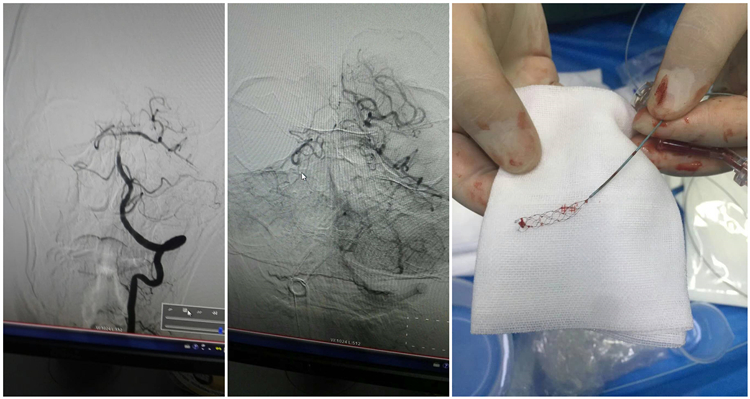

另一名患者,中年男性,基底动脉急性血栓形成,病情进展及其迅速,由头晕起病迅速意识丧失,生命体征极不稳定,病理生理体征均不能引出,经东西两院急诊科共同协作,开通卒中绿色通道,气管插管下完成机械取栓术,现患者生命体征平稳,病生理反射可引出,于EICU进一步康复治疗中。